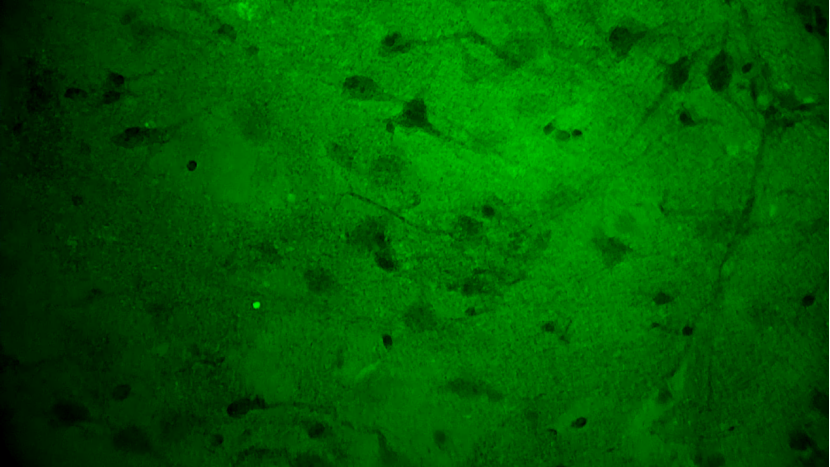

關(guān)顱期間,專家團隊將其余3塊瘤體組織應(yīng)用EndoSCell?掃查以觀察腫瘤細胞形態(tài),無一例外,3塊組織的細胞圖像均符合“核異型性明顯、分布密集且不規(guī)則”的腫瘤形態(tài)特征,其中一塊還意外發(fā)現(xiàn)了清晰的神經(jīng)元細胞。EndoSCell?高清直觀的細胞圖像給專家們留下了深刻印象,參與本次手術(shù)的張帥專家表示有合適機會或?qū)L試在體應(yīng)用。

神經(jīng)元細胞:神經(jīng)纖維束清晰、密度低